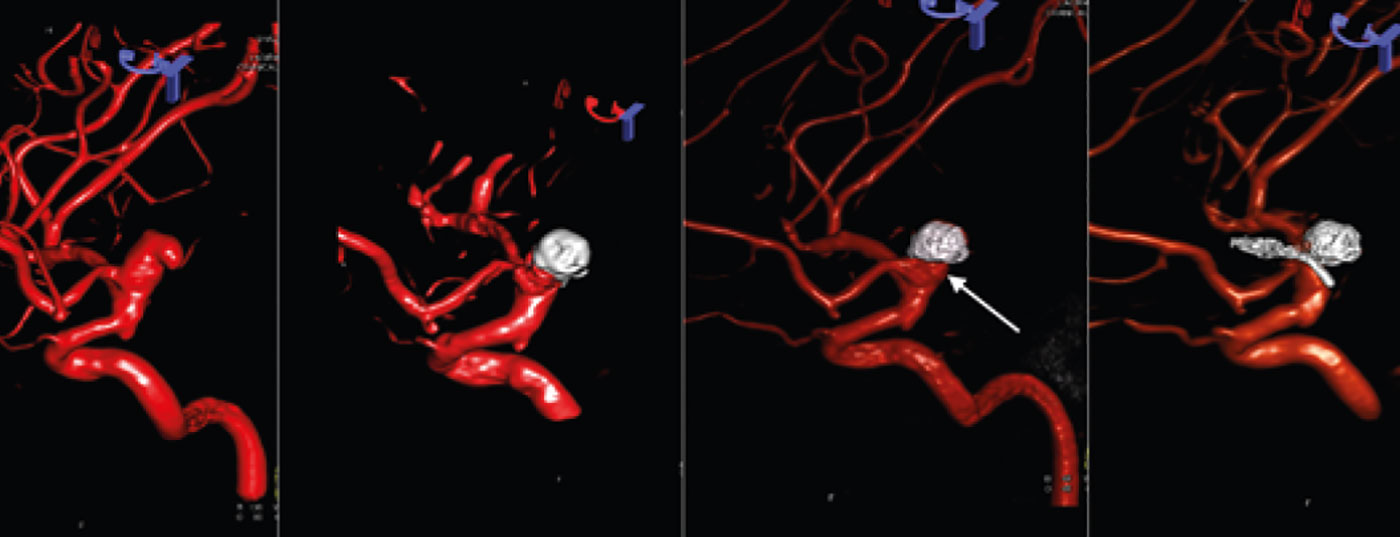

Wie entscheiden bei der Aneurysma­therapie?

Behandlungsziel bei intrakraniellen Aneurysmen ist die Ausschaltung des Aneurysmas. Die Hauptbehandlungsmethoden bestehen aus Clipping und Coiling. Beim Behandlungsentscheid sind verschiedene Aneurysma- und Patienten-spezifische Faktoren zu berücksichtigen.